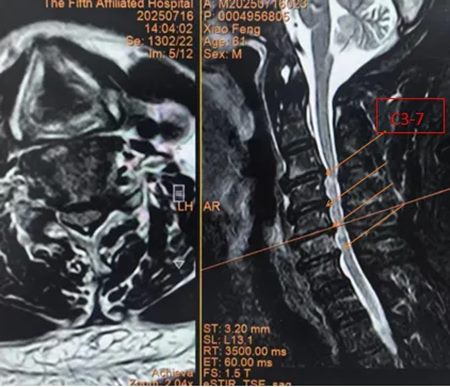

肖先生(化名)曾长期被四肢麻木、写字颤抖、行走不稳困扰,保守治疗效果不佳,症状持续加重。经过多方求医,来到郑州大学第五附属医院,经颈椎核磁检查显示:C3-C7节段严重椎管狭窄,椎间盘突出导致脊髓严重受压。

▲ 术前MRI